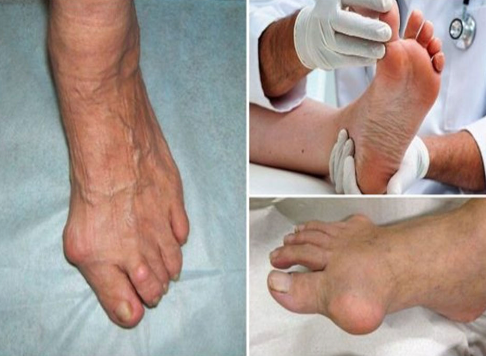

발가락 진단 및 의료 평가

언제 병원을 찾아야 할까?

만성적이거나 심한 발가락 통증을 경험한다면 의료 전문가와 상담하는 것이 중요합니다. 조기 진단과 치료는 추가 합병증을 방지하는 데 도움이 됩니다.

진단 검사

발가락 통증의 원인을 파악하기 위해 의료 전문가는 X-선, 초음파 또는 MRI 검사를 포함한 다양한 진단 검사를 수행할 수 있습니다.